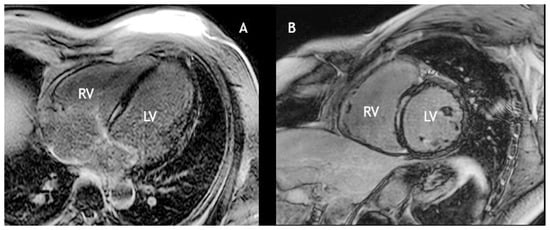

On physical examination he appeared in excellent condition, with weight 90 kg for a height of 185 cm. The pulse was regular and bradycardic at 39 bpm, blood pressure was 130/80 mm Hg. Cardiac and chest auscultation were unremarkable. Chest x-ray showed a slightly dilated cardiac silhouette. The ECG revealed sinus rhythm with 2:1 atrioventricular block (AVB) (Figure 1) alternating with complete AVB (Figure 2). During Holter monitoring there was normal sinus rhythm with persistent high-degree AVB (Mobitz type 2; advanced second degree – 2:1 and 3:1 – and complete AVB) with mean ventricular rate 41 bpm and maximum R-R interval of 4 s. An echocardiogram revealed mild left ventricular dilatation (left ventricular end-diastolic diameter 62 mm), and a subnormal left ventricular ejection fraction (LVEF) of 50% due to septal hypokinesia. Cardiac magnetic resonance imaging (CMR) confirmed the mild left ventricular dilatation and showed linear mid-myocardial late gadolinium enhancement of the basal septum, indicating myocardial fibrosis (Figure 3). On the basis of the family history of DCM, the complete AVB, the mild left ventricular dilatation with sub-normal LVEF and linear mid-myocardial septal fibrosis, we suspected cardiomyopathy due to a lamin A/C (LMNA) gene mutation.

Figure 3. Post-contrast inversion recovery gradient echo images (late gadolinium enhancement) in a four-chamber (A) and short axis view (B), showing linear, mid-myocardial enhancement of the basal ventricular septum, consistent with fibrosis.

In addition to history, ECG and echocardiography, CMR plays an important role in determining cardiac involvement in LMNA cardiomyopathy. Holmström et al. [16] showed that 88% of patients with LMNA cardiomyopathy had left ventricular myocardial fibrosis. The pattern of enhancement was typically linear and less than 50% of the area of the segment. In all the patients, late gadolinium enhancement occurred in the basal or mid-ventricular septum, which strongly correlated with segmental wall motion abnormalities. Our patient had exactly this typical pattern.